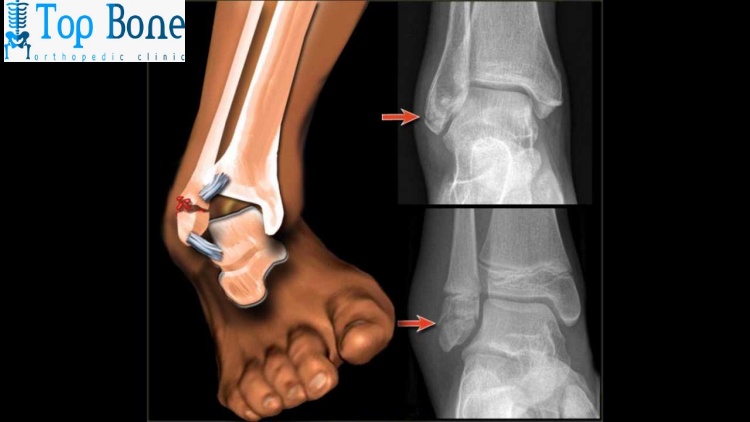

ما بعد عملية الشرائح والمسامير في الكاحل؟

ما بعد عملية تركيب الشرائح والمسامير في الكاحل يتطلب عناية خاصة لضمان الشفاء التام والعودة إلى النشاطات اليومية بأمان، في الأيام الأولى بعد الجراحة، يكون من الضروري الحفاظ على القدم المصابة مرتفعة لتقليل التورم.

واستخدام كمادات الثلج في حال توجيه الطبيب لذلك. يجب تجنب وضع أي وزن على الكاحل المصاب، ويمكن استخدام العكازات أو أجهزة دعم أخرى للتنقل بأمان، من المهم أيضًا الحفاظ على نظافة الجرح وتغيير الضمادات بشكل دوري حسب تعليمات الطبيب.

خلال فترة التعافي، قد يحتاج المريض إلى تناول مسكنات للألم والمراجعة الدورية للطبيب لمتابعة تقدم التئام العظام في بعض الحالات، قد يتطلب الأمر الخضوع لجلسات علاج طبيعي لاستعادة القوة والحركة في الكاحل، والتي يمكن أن تستمر عدة أسابيع أو أشهر، تواصل معنا الان لمعرفة تكلفة عملية الشرائح والمسامير.

قد يحتاج المريض أيضًا إلى إجراء أشعة سينية للتأكد من أن العظام تلتئم بشكل صحيح و يختلف وقت التعافي من شخص لآخر، لكنه يتراوح عادةً بين 3 إلى 6 أشهر، ويعتمد على شدة الكسر ومدى التزام المريض بالتعليمات الطبية، تواصل معنا في مركز توب بون لمعرفة تكلفة عملية الشرائح والمسامير.